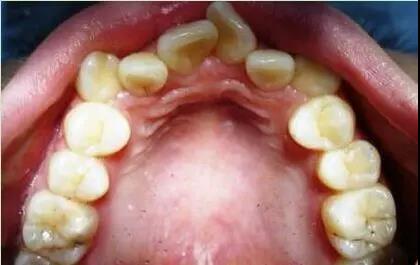

随着人类的繁衍进化,人类的头部比例发生了很大的变化。大脑所占的体积越来越大,上下颌骨的体积却越来越小。而上下颌骨就是牙齿的家,家的面积越来越小,导致人类的32颗牙齿不能很整齐的排成完美的弧形,而最直观的结果就是牙列拥挤、龅牙。

我国,牙周炎已成为成年人牙齿缺失的首因,关键致病因素是口腔的菌斑微生物。美国人防范牙周病的意识很强,他们会定期洗牙,杂乱的牙齿更是在少年时期进行矫正!因为牙齿的杂乱使口腔清洁变得困难,容易滋生更多的牙菌斑,导致牙周疾病的产生。